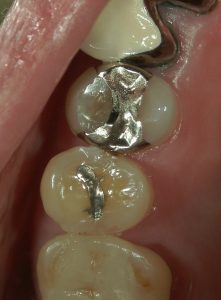

治療前の写真です。

銀歯を除去すると中はむし歯により傷んでいました。

銀歯での治療ではこのようにむし歯が再発・進行しやすい環境であるため短い期間で再治療が必要となり、更に神経を失うリスクが高まってしまいます。